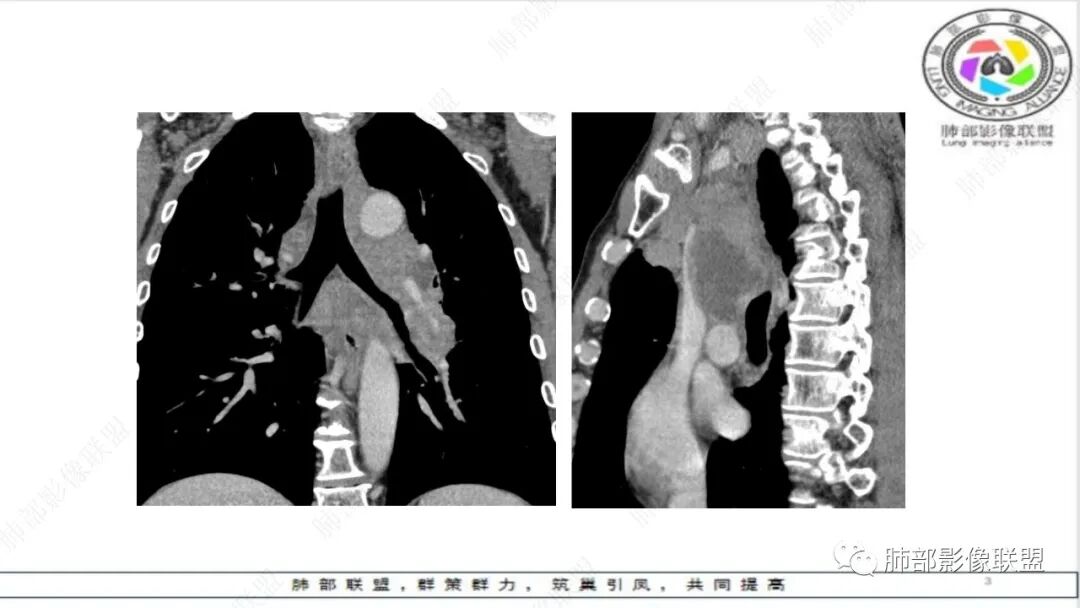

纵隔内及左肺门淋巴结肿大,冰冻纵膈,肺动脉包绕受压,支气管受压变窄,呈针孔样。双肺上叶结节及条索考虑陈旧结核。老年男性,慢支肺气肿背景,考虑小细胞肺癌。左肺上叶后段大片实变,不符合小细胞肺癌原发灶,二元论感染灶?肺栓塞?

晨读:男,65,咳喘1月余,加重3天。胸部CT:纵隔、肺门多发淋巴结肿大融合,冰冻纵隔,冰冻肺门,大血管包埋挤压,左肺A主干变窄。平扫密度较均匀,不均匀强化,灶性低密度。右上肺多发实性结节,中轴间质分布;左上叶针孔状支气管,后段胸膜下近楔形斑片影,融冰?考虑Ca,SCLC,并左上叶PTE?鉴别淋巴瘤。

“鸭蹼状”、“腊肠样”凸起

冰冻肺门多于冰冻纵隔,与淋巴引流方向一致,淋巴转移先增值扩大,然后侵犯周围组织

鸭蹼状凸起一般比较圆钝,边缘清,走行与支气管一致

腊肠样凸起,粗细相对均匀,与支气管走行一致

”娘小崽大“原发灶一般较小,转移灶很大